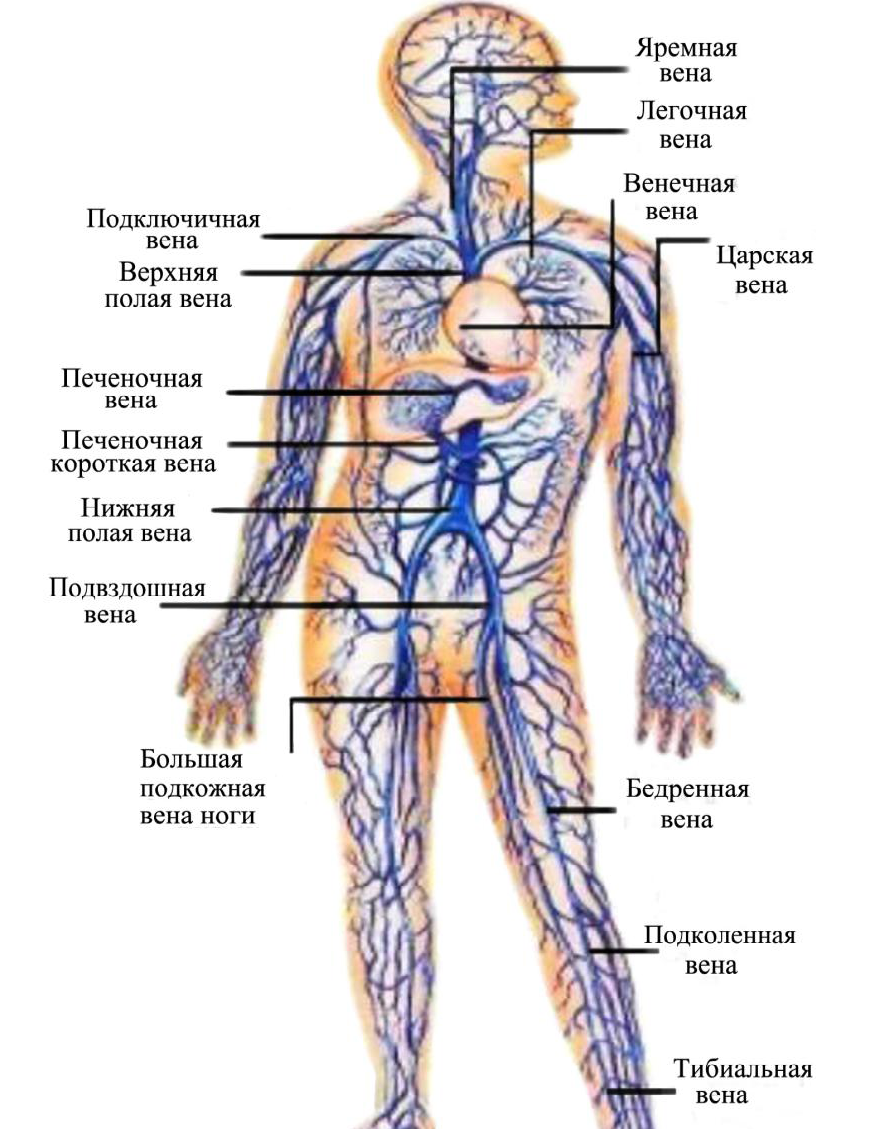

Анатомия человека: кровеносная система и её связь со скелетом